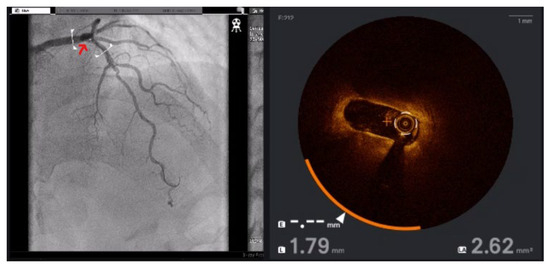

Reviewing Strategies and Our Approach to Mapping and Ablation of Left Ventricular Summit Arrhythmias

by Ziad Abuiznait, Mohamad Ghanayem, Nizar Andria, Ali Sakhnini, Edo Birati and Ibrahim Marai

Background: Left ventricular (LV) summit is an important origin for ventricular arrhythmias (VAs). However, the complex electroanatomic structure of LV summit and the surrounding anatomic sites makes ablation of this arrhythmia challenging. Aim: In this paper, we review the main strategies to mapping [...] Read more.

Background: Left ventricular (LV) summit is an important origin for ventricular arrhythmias (VAs). However, the complex electroanatomic structure of LV summit and the surrounding anatomic sites makes ablation of this arrhythmia challenging. Aim: In this paper, we review the main strategies to mapping and ablation of LV summit VAs and summarize our experience in this challenging ablation. Methods: To summarize our experience, we included all consecutive patients with outflow VAs referred to our institute for ablation between 2019 and 2024 who were eventually diagnosed with LV summit origin based on electroanatomical mapping and ablation result using stepwise and sequential ablation approach. Results: A total of 38 patients were found to have VAs from LV summit origin. Overall five patients had history of at least one failed ablation. V1 transition was seen in 15 patients, V2 transition in 12 patients, and V3 transition in 11 patients. Four patients had R wave pattern break in lead V2. Ablation was performed from the earliest activation or from one of the adjacent sites using stepwise and sequential approach. Acute suppression of VAs occurred in 35 patients without complications, except one case of pseudoaneurysm of femoral artery. Conclusions: Stepwise and sequential ablation approach can suppress VAs originating from LV summit in most patients. Full article